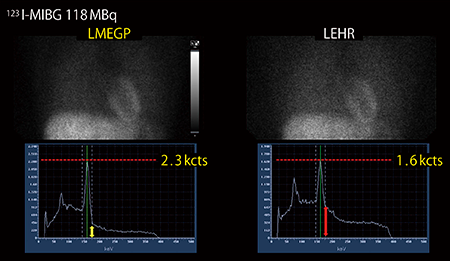

検出器に装備されるコリメータにも大きな特長がある。標準装備である低中エネルギー汎用(以下,LMEGP)コリメータは,感度と分解能,ペネトレーションという相反関係にあるパラメータを徹底的に検討し,心筋SPECT検査に最適化したコリメータである。

低エネルギー高分解能(LEHR)コリメータと比較して約1.8倍の感度があり,効率良くγ線計測が可能なため,心電図同期収集や99mTc製剤に比べてカウントが得られにくい201Tl製剤でも安定して画像を提供することができる。

また,123I核種に見られる529keVに由来する高エネルギー側散乱線成分の混入を抑え,心縦隔比(HMR)の定量性が改善される(図3)。このように,LMEGPコリメータ一つで核種によらず心臓検査全般に対応できる。

図3 LMEGPコリメータとLEHRコリメータの比較

(データご提供:国立循環器病研究センター様)